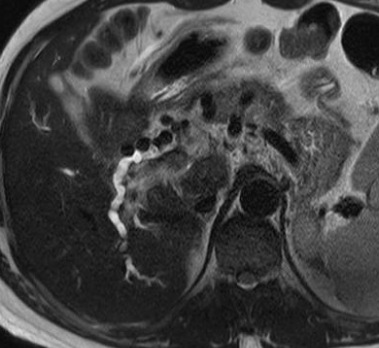

- Sur thrombose porte chronique ++

- Voie de dérivation Porto-Porte (contrairement à porto-systémique du reste de l’hypertension portale)

- Péri-veine porte et Lit vésiculaire ++

- Le Cavernome se développera surtout sur un foie sain avec occlusion porte rapide

Biliopathie portale

- La dilatation des petites veinules péri-biliaires peut compresser les voies biliaires (sorte de Mirizzi) → Biliopathie portale = dilatation souvent asymptomatique des VB